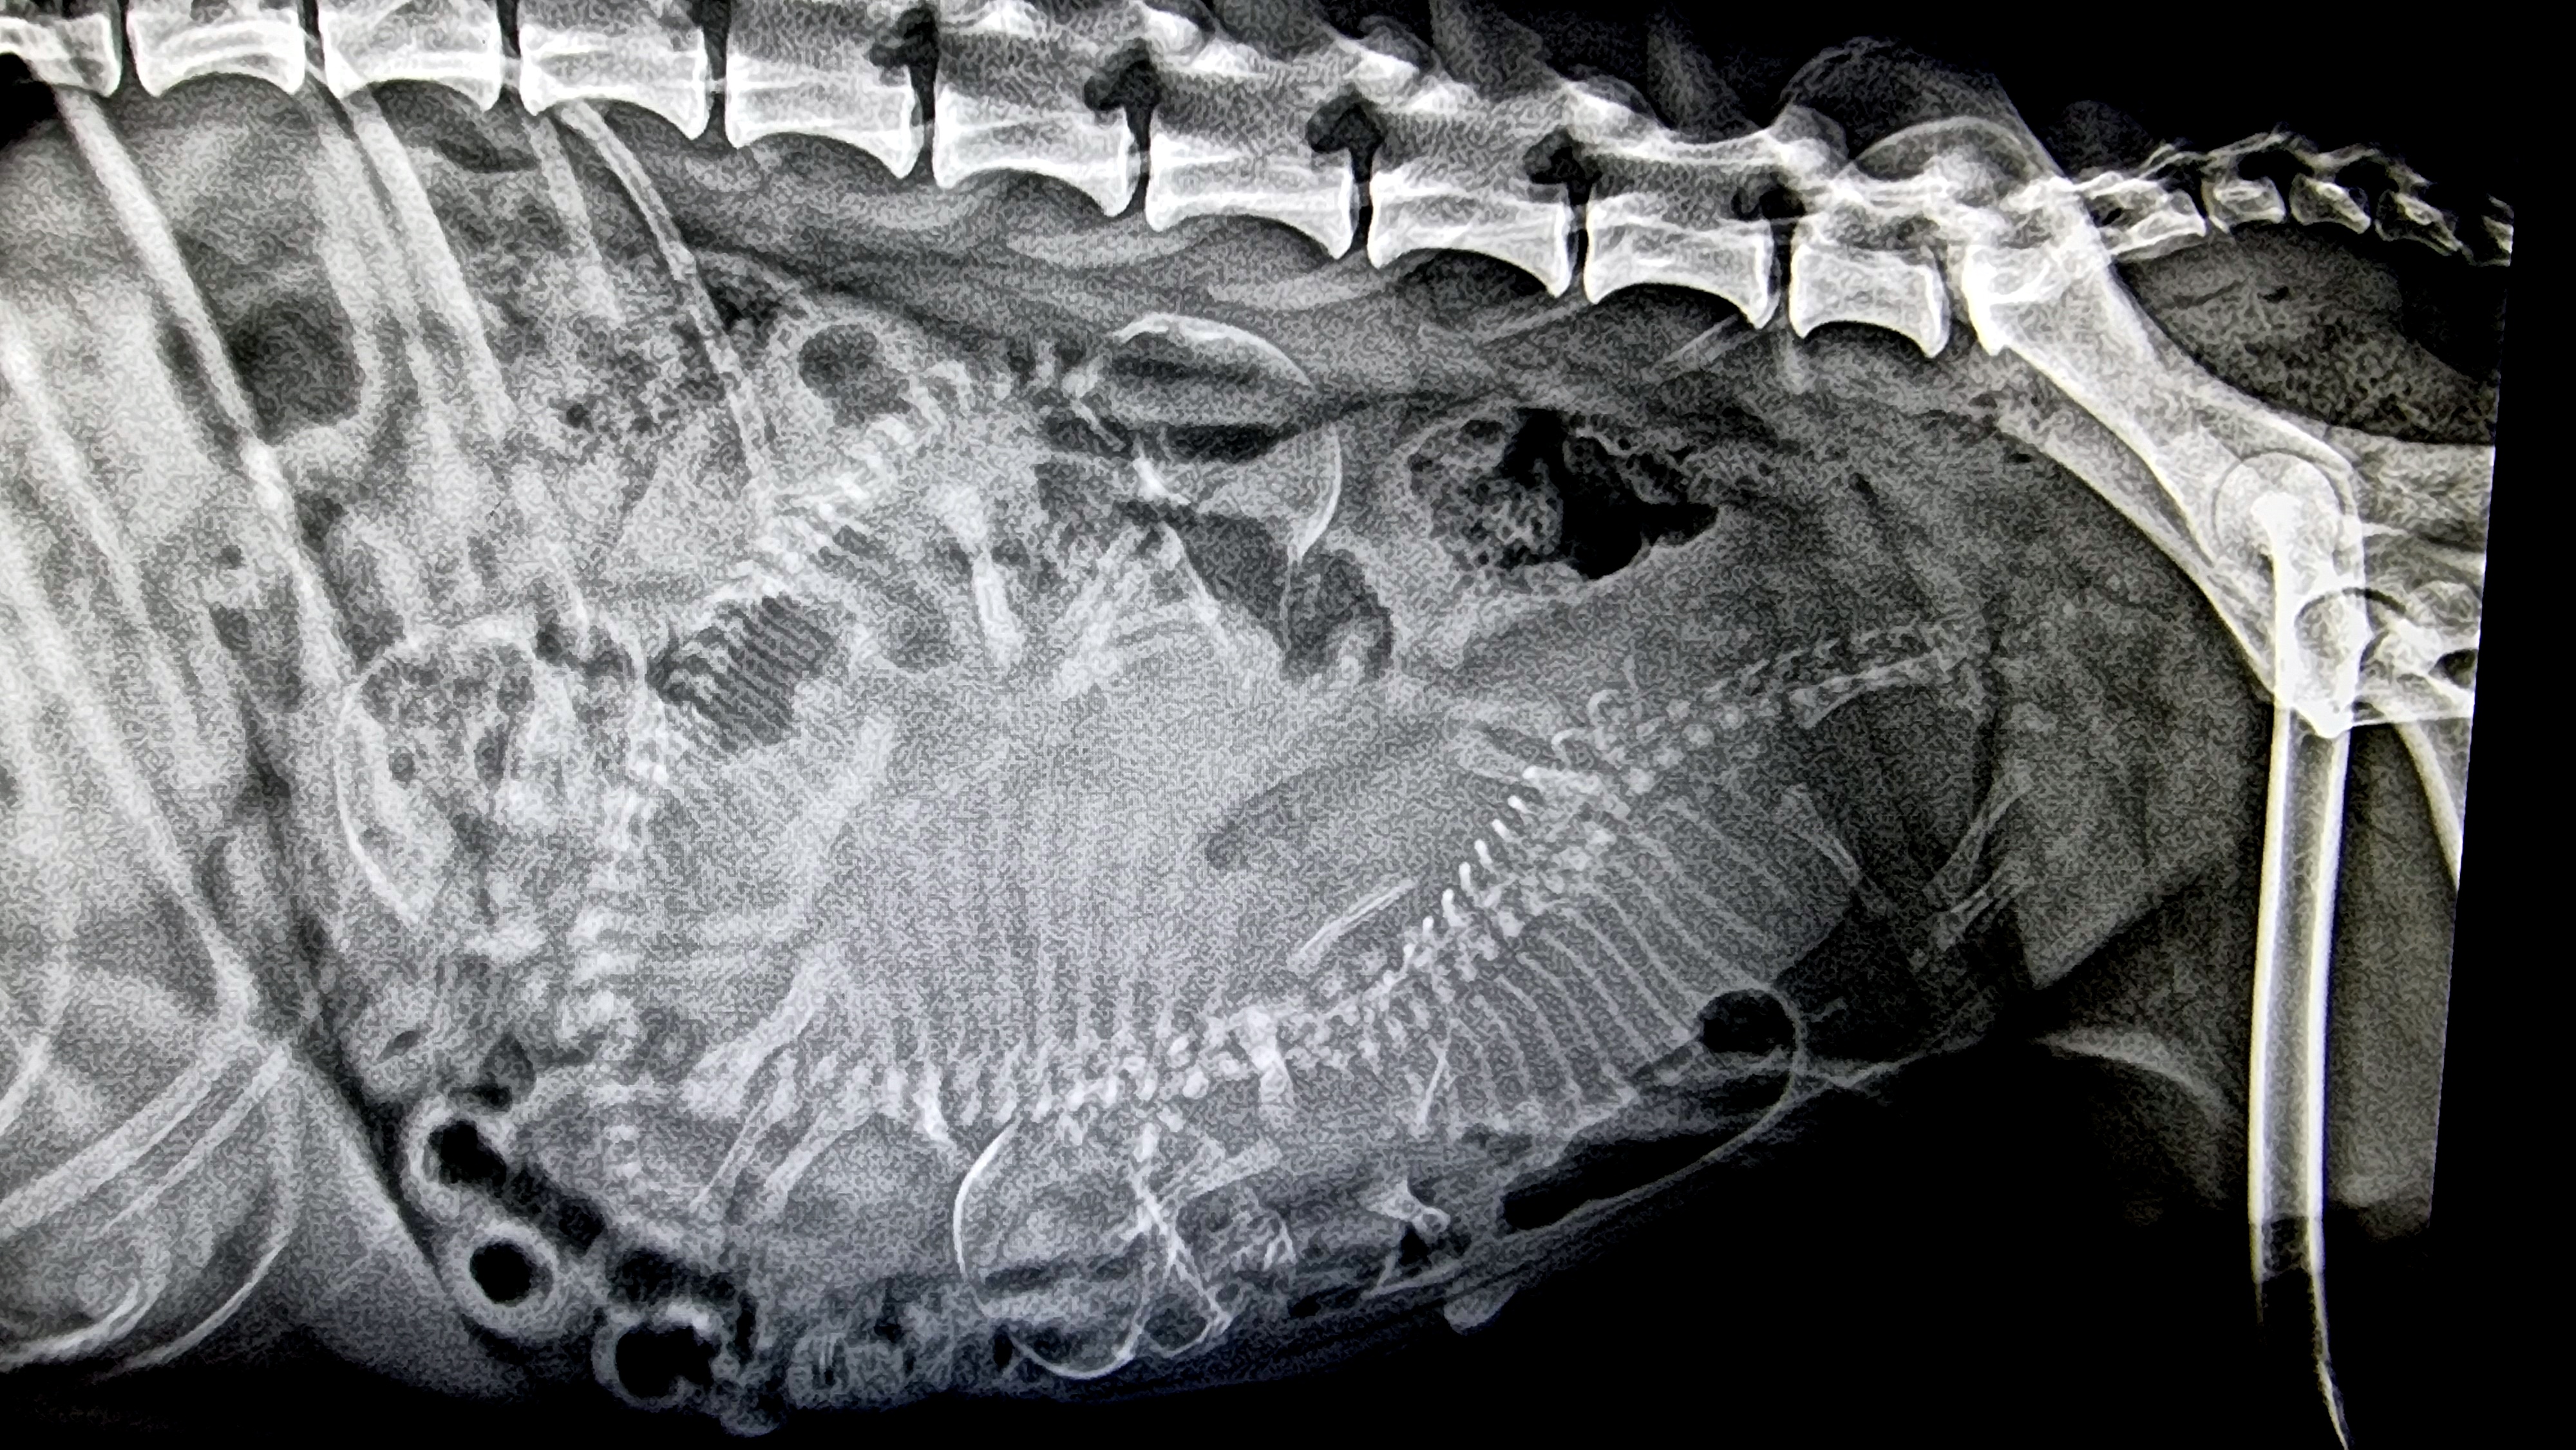

Ine er i siste uke i drektigheten og kan nå føde når som helst. på rtg kan man se 3 valper. Så spent på hvem disse 3 er. Og det får jeg forhåpentlig vite i løpet av uka – blir lang ventetid